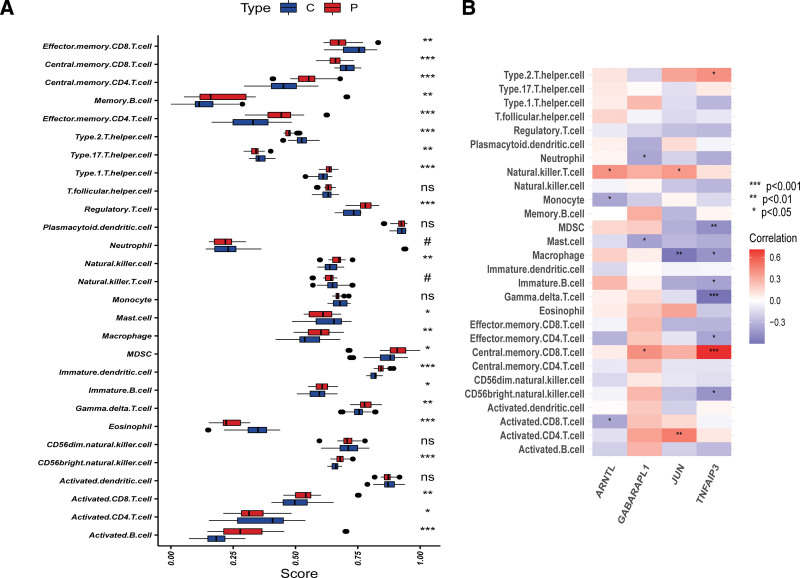

3.6. Immunological infiltration in the OA group and healthy controls using ssGSEA analysis

The results of ssGSEA showed that the proportion of Effector memory CD8 T cell, Central memory CD8 T cell, Type 17 T helper cell, Type 2 T helper cell, Mast cell, Eosinophil, and Activated CD4 T cell in OA samples were significantly lower than in normal control samples However, Central memory CD4 T cell, Memory B cell, Effector memory CD4 T cell, Type 1 T helper cell, Regulatory T cell, Natural killer cell, Macrophage, MDSC, Gamma delta T cell, Immature B cell, Immature dendritic cell, CD56 bright natural killer cell, Activated CD8 T cell, and Activated B cell in OA samples were significantly higher than in normal control samples (Fig. 8A). These results revealed that immune infiltration status had a significantly difference in OA samples, which advanced our comprehending of mechanism in OA. Correlation analysis shown that JUN was associated with Activated CD4 T cells, Macrophage, and Natural killer T cell (Fig. 8B). Our founding suggested that feature genes have an underlying impact on immune cells component.

It has become increasingly apparent that immunocyte infiltration plays a major role in the pathogenesis and development of OA.[40,41] Arthritis foci of OA has been reported to contain abundant infiltration of CD4 + T cell. CD4 + T cell induce Th1-type immunity, which mediates with increased production of immune regulatory cell factors.[42,43] Inflammation and immunity response contribute to disease progression of OA. Previous study of Rosshirt had also raised that CD16+/CD56 + natural killer cells, CD8 + T cells, CD4 + T cells, and macrophages were also highly enriched in OA joints.[44] Therefore, it is necessary to gain a comprehensive understanding the immune response inside the foci of OA regarding interactions between immune cells and their microenvironment to provide new ideas and target for the clinical therapy of OA. In the present study, we observed that the levels of Effector memory CD8 T cell, Central memory CD8 T cell, Type 17 T helper cell, Type 2 T helper cell, Mast cell, Eosinophil, Activated CD4 T cell, Central memory CD4 T cell, Memory B cell, Effector memory CD4 T cell, Type 1 T helper cell, Regulatory T cell, Natural killer cell, Macrophage, MDSC, Gamma delta T cell, Immature B cell, Immature dendritic cell, CD56 bright natural killer cell, Activated CD8 T cell, and Activated B cell presented significant difference in the levels of cell infiltration between OA and normal tissue samples. We also investigated the correlation between the expression of GABARAPL1, TNFAIP3, ARNTL, and JUN and infiltrating levels of various immune cell. We found that GABARAPL1 was correlated with Central memory CD8 T cell, Mast cell, and Eosinophil; TNFAIP3 was correlated with Type 2 T helper cell, MDSC, Macrophage, Gamma delta T cell, Immature B cell, Effector memory CD4 T cell, Central memory CD8 T cell, and CD56 bright natural killer cell; ARNTL was correlated with Natural killer T cell, Monocyte, and Activated CD8 T cell. Moreover, we found that JUN was correlated with Activated CD4 T cell, Macrophage, and Natural killer T cell. From above observations, we speculated that GABARAPL1, TNFAIP3, ARNTL, and JUN affects immune responses and disease process of OA by influencing immunocytes infiltration. Further work into a complex array of immune players acting in concert behind immune response in OA is required to confirm these hypotheses.